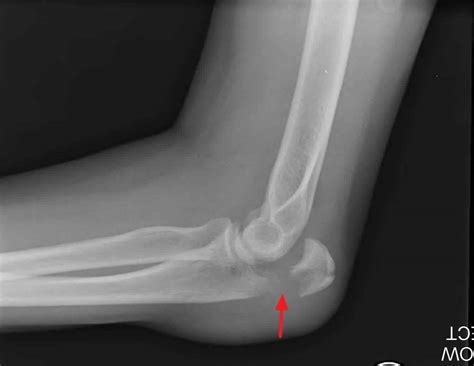

Doctors will typically use X-rays to visualize the bones and confirm a diagnosis. In more complex cases, such as intra-articular fractures, a CT scan might be required to determine if surgical intervention is necessary to realign the bone fragments.

- broken elbow pictures